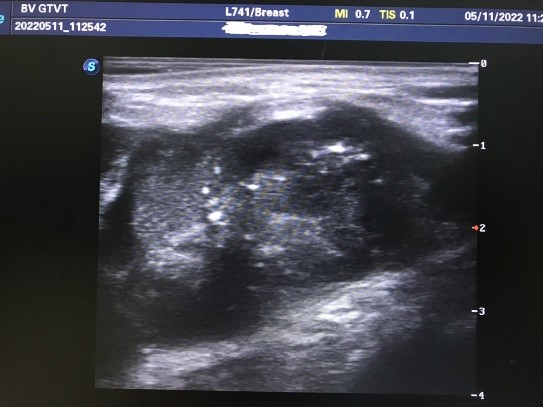

Tại khoa Chẩn đoán hình ảnh bệnh nhân được thực hiện siêu âm bởi Ths. Bs. Trần Xuân Bách, kết quả cho thấy bệnh nhân có khối giảm âm vú trái kích thước khoảng 50x30mm, bờ không đều, bên trong có vi vôi hóa và có vài hạch bất thường hố nách bên trái.

Hình ảnh siêu âm khối u vú trái ( BIRADS V)